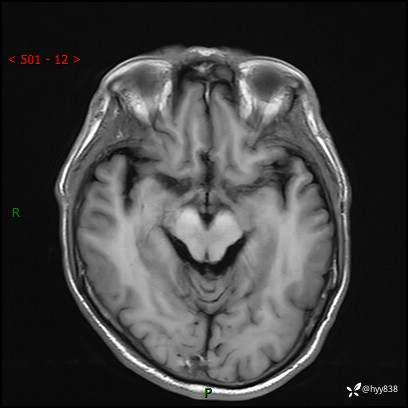

颅脑MRI平扫